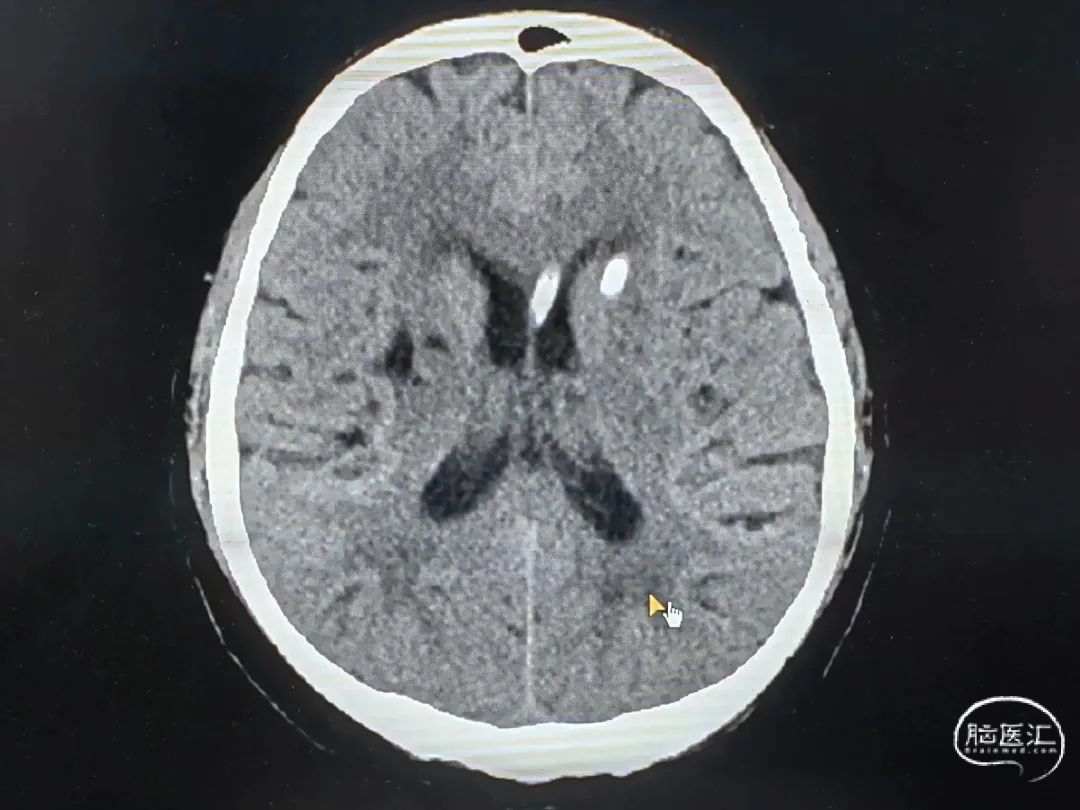

CT扫描后测算脑干血肿穿刺靶点及路径

脑室及血肿腔平行双管

脑干血肿引流管经大脑脚入中脑

引流管穿经中脑血肿

引流管准确到达靶点